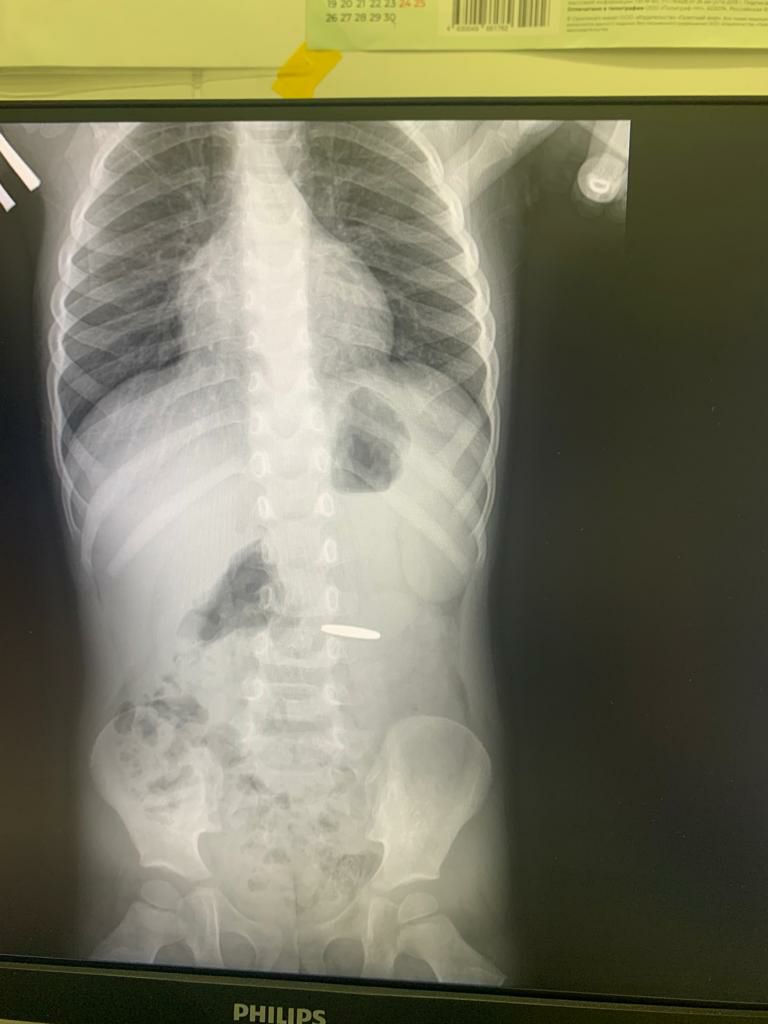

«Сто ребенок проглотил монету, родители узнали сразу, это подтвердил и рентген, который сделали по обращению в больницу, — рассказал заведующий отделением эндоскопии Туапсинской центральной районной больницы №1 Гор Саакян.

— Однако понадеялись, что она выйдет естественным путем. Ребенок принимал пишу все это время, но результатов не было. Вчера ришли к нам. Ребенку сделали анализы, рентгеновский снимок, провели консультации педиатра , затем анестезиолога, а затем провели лечебную гастроскопию. В итоге монету извлекли.